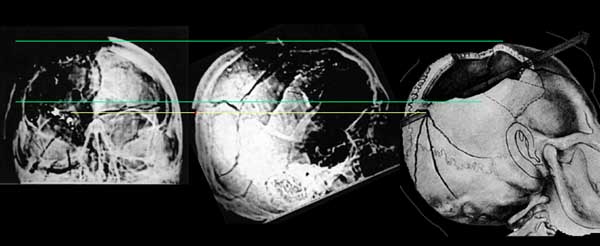

I rotated the drawing and drew a yellow line to mark the entrance wound location and green lines to mark the upper and lower boundaries of the skull defect. These match up quite well.

http://mcadams.posc.mu.edu/xray/dox/dox.htm

My own interpretation is below. Although it is not a perfect match, it is fairly close.

Vergleich mit der Perspektive der Hinterkopffotos